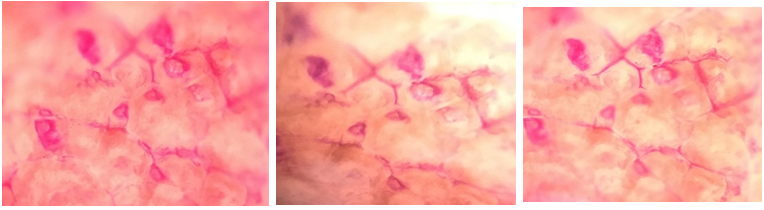

Pig-ear skin that was quickly gathered after pigs were slain at a nearby slaughterhouse was used for in vitro skin insertion research. Damaged skin was scraped from skin samples after they had been cleansed with cold water. The entire skin was meticulously separated from the underlying cartilage to generate full-thickness skin membranes. The skin was defrosted and sliced into 2*2 cm squares before the diffusion tests. Thumbtacks were used to secure the skin samples into a firm framework before the microneedle arrays adhered to their surface. The skin was physically compressed with microneedles for 30 seconds with force comparable to pressing an elevator button or a stamp into an envelope; then, the compression site was peeled off and exposed to a fluorescent dye for 1 minute. Skin samples that were treated for histological analysis had the remaining dye removed. Skin samples were fixed in 10% formalin, dried, and embedded in paraffin to create histology specimens [29]. To evaluate penetration depth, skin samples were stained with methylene blue dye and examined under an Olympus fluorescence microscope as shown in fig. 10.

Fig. 10: Microscopic Image of pierced porcine skin using fabricated microneedles observed at 40X